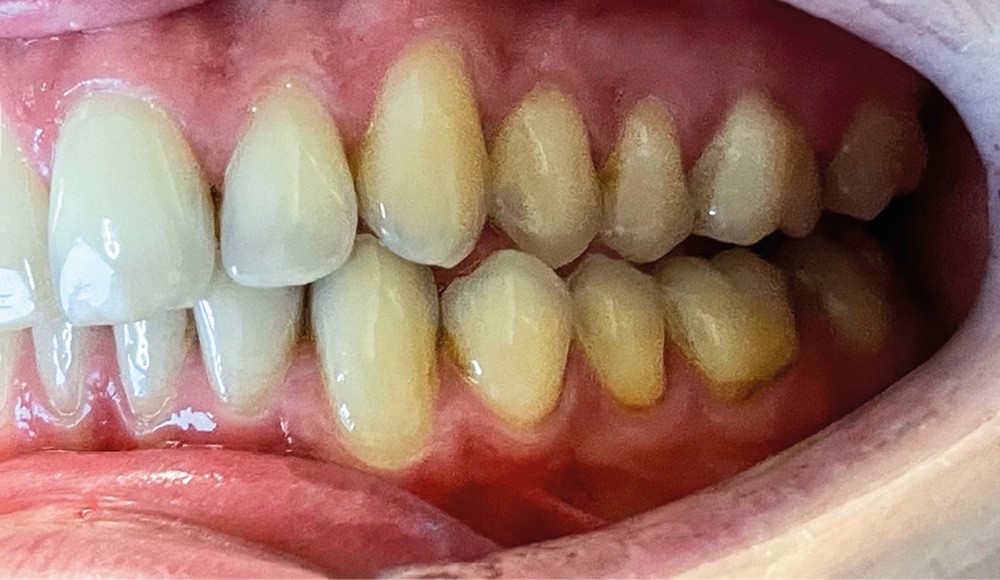

► L’entretien semi-directif met en évidence des signes d’apparition récente (un an environ), une aggravation progressive des symptômes, et la perception rapportée par le patient de moindres contacts occlusaux du côté gauche. L’examen clinique extra-oral révèle des douleurs musculaires lors de la palpation des muscles masséters, temporaux et ptérygoïdien médial gauche ainsi que des muscles sterno-cléïdo-occipito-mastoïdiens droit et gauche. Il n’y a pas de limitations d’ouverture buccale. L’examen clinique intra-oral révèle la présence d’une inocclusion dentaire gauche, qui s’étend des dents 23 à 27 (fig. 1 et 2). Il est à noter que la reprise de l’entretien ne rapporte pas d’antécédent de soins dentaires, orthodontiques et/ou prothétiques susceptibles d’engendrer une modification de l’occlusion.

► Les examens radiographiques 3D à type de CBCT permettent de mettre en évidence un condyle gauche plus volumineux que le condyle droit, et un bord basilaire gauche plus bas que le droit (fig. 3 et 4), provoquant une asymétrie dans le sens frontal, avec une mandibule abaissée vers le bas et vers l’avant. Le diagnostic d’une hypercondylie mandibulaire est évoqué avec le patient.